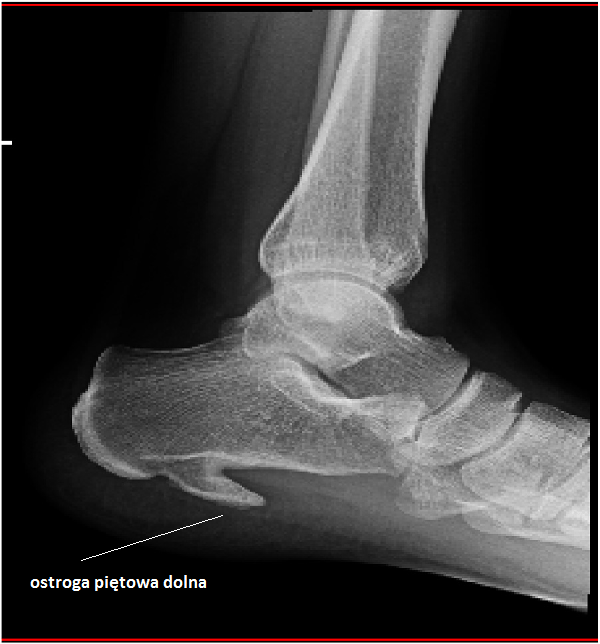

Dość często zdarza się, że ból pięty przy chodzeniu spowodowany jest ostrogą piętową. Jest to niewielkie zwapnienie na kości piętowej, które podczas poruszania się drażni okoliczne tkanki miękkie powodując silny ból i stan zapalny. Ból pięty w trakcie chodzenia w przypadku ostrogi piętowej pacjenci opisują jako kłujący i przeszywający. Ból pięty najsilniejszy jest rano, gdy stopy nie są jeszcze „rozchodzone”. W miarę kolejnych kroków ból maleje, ale nie znika zupełnie. Dopiero spoczynek i rozmasowanie stopy przynosi pacjentowi pewną ulgę. Leczenie ostrogi piętowej polega na noszeniu specjalnych wkładek ortopedycznych, które muszą być idealnie dopasowane do stóp pacjenta. Pięta jest w nich odciążona, by dać szansę chorym tkankom na wygojenie się. Druga kwestia to terapia falą uderzeniową, której skuteczność w leczeniu ostrogi piętowej sięga aż 80% falą rozproszoną (radialną) i nawet 90% w przypadku terapii falą skupioną! Niekiedy już po kilku zabiegach ból pięty zmniejsza się, tak samo jak stan zapalny. W zdecydowanej większości przypadków w leczeniu ostrogi piętowej zalecamy wykonanie pełnej serii, a więc 8 zabiegów falą skupioną. Zdarzają się jednak przypadki, rzadko bo rzadko, że tych zabiegów potrzeba wykonać więcej. Ból pięty przyczyny, poniżej kolejne schorzenia…

Ostroga piętowa

To podstawowe badanie obrazowe przy bólu pięty. Na zdjęciu RTG widać:

• Ostrogę piętową – zwapnienie na kości piętowej

• Złamania lub pęknięcia kości piętowej

• Zmiany zwyrodnieniowe w stawie podskokowym

RTG NIE POKAŻE: stanu zapalnego tkanek miękkich, uszkodzeń ścięgien, rozcięgna podeszwowego. Dlatego często potrzebne jest USG.